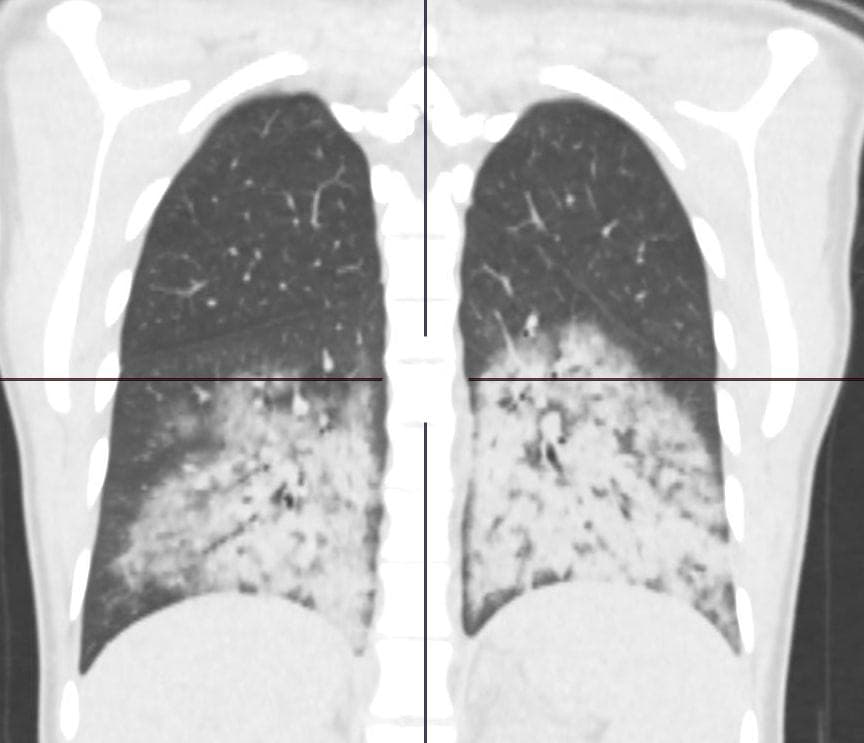

Главврач Коммунарки (главного ковидного госпиталя Москвы) Денис Проценко опубликовал фото лёгких курильщика вейпов и электронных сигарет. Он объяснил, что электронные средства приводят к новой болезни лёгких — EVALI — E-cigarette, or vaping, product use associated lung injury — повреждение лёгких вследствие курения E-сигарет.

К чему приводит курение электронных сигарет и вейпинг? К появлению нового заболевания — EVALI — E-cigarette, or vaping, product use associated lung injury. Сегодня такая пациентка оказалась в отделении реанимации нашей клиники. 20 лет ребёнку, — опубликовал пост в своём Telegram-канале Проценко.

EVALI характеризуются определённой КТ-картиной «матового стекла». Американские медики отметили, что E-сигареты сильно нагревают смесь никотина, ароматизаторов и других химических соединений, которые попадают в организм при вдохе. За последние 10 лет использование таких сигарет и вейпов многократно увеличилось.